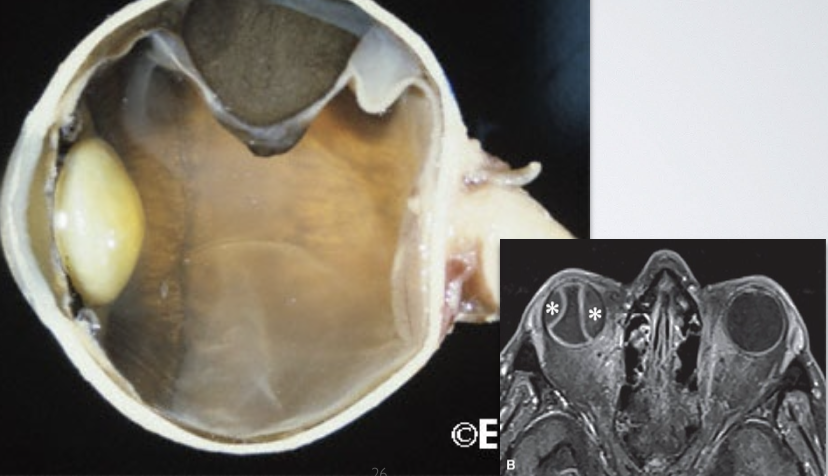

What role does Bruch’s membrane play when a tumour expands in the choroid?

due to its elastic layer, the Bruch’s membrane is very effective at preventing expanding masses (tumours) from breaking through the retina